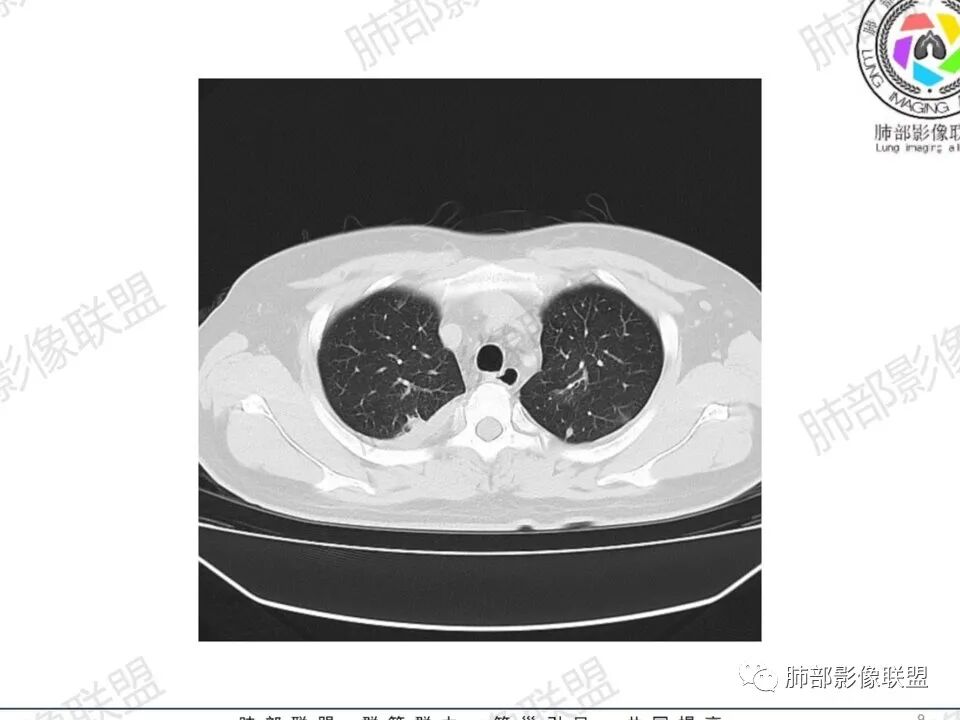

双肺多发结节,胸膜下为主,部分可见空洞。左肺上叶尖后段结节较大,分叶毛刺,周围可见长条索及小斑片影,内空洞比较光滑,内侧壁可见支气管通过。右肺下叶后基底段不张实变,后侧积液,右侧水平裂积液,右侧膈胸膜纵膈胸膜增厚积液,右侧侧胸膜肥厚,考虑1:一元金葡。2二元:金葡,左肺上叶结核。

男,45岁,左手指红肿疼痛两天,右侧胸壁疼痛伴发热12小时入院。患者急性起病,胸部CT示双肺多发结节,部分伴空洞,空洞壁较光滑,右侧胸腔积液,考虑感染性病变,金葡菌加SPE可能

尘缘: @赵永兵 内蒙巴市临河妇幼影像科 左上肺也是胸膜下(胸膜顶下)的SPE。

@赵永兵 内蒙巴市临河妇幼影像科 支气管是从旁边经过,所以不是空洞,是胸膜下的脓毒栓。如果是结核空洞,应该与支气管相通(因为结核没有血播感染表现的时候,来源是气道,空洞应该与支气管相通),所以支气管从旁边经过,这病灶又在胸膜下,周围也没有干酪坏死。当然是SPE了。

中年男性,左手中指及胸壁疼痛伴发热来诊,影像见双肺多发结节,胸膜下分布为主,部分结节可见空洞,边缘模糊。左肺上叶尖后段结节较大。右肺下叶后基底段不张实变,右侧叶间裂及右侧胸腔积液,右侧侧胸膜肥厚。考虑金葡菌感染,血播SPE。

胸膜下为主多发结节,边缘光滑

伴随楔形影,支气管壁不增厚